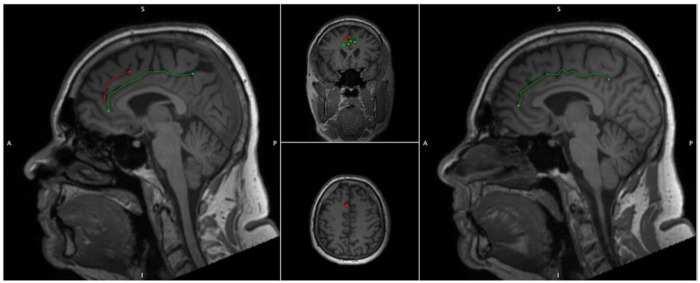

The Anterior Cingulate (AC) is a highly heterogenic medial frontal lobe gyrus with extensive interindividual variability and asymmetry. Variability may be classified in accordance with the presence of a Paracingulate Sulcus (PCS), a tertiary sulcus, which when present develops during the third trimester of gestation and remains stable thereafter, unaffected by maturation or environmentally induced neuroplastic changes (ref. Chi, Dooling et al. 1977, ref. Del Maschio, Sulpizio et al. 2019). The PCS denotes the existence a respective Paracingulate Gyrus (PCG). In healthy individuals there is an established leftwards-dominance of PCS presence (presence of a left, but not right hemisphere PCS), as displayed in Fig. 1. (ref. Paus, Tomaiuolo et al. 1996, ref. Yücel, Stuart et al. 2001, ref. Yücel, Stuart et al. 2002, ref. Le Provost, Bartres-Faz et al. 2003, ref. Huster, Westerhausen et al. 2007, ref. Leonard, Towler et al. 2009, ref. Wei, Yin et al. 2017, ref. Amiez, Wilson et al. 2018, ref. Selahi, Kuru Bektaşoğlu et al. 2022). Whilst reported frequencies vary PCS are present in approximately 70–75% of left hemispheres and 50–60% of right hemispheres in the healthy population (ref. Paus, Tomaiuolo et al. 1996, ref. Yücel, Stuart et al. 2001, ref. Fornito, Yücel et al. 2004). The PCG is active during performance of a variety of cognitively demanding tasks drawing on higher-order executive function. (ref. Fornito, Yücel et al. 2004) (Carter et al., 1998; Duncan and Owen, 2000). A performance advantage across several verbal and non-verbal higher-order functions utilising effortful cognitive control and verbal and spatial working memory has been observed in individuals possessing a leftward asymmetry of PCS presence (ref. Fornito, Yücel et al. 2004) (Whittle, Allen et al. 2009). Similarly, individuals with asymmetric PCS patterns display greater inhibitory control and cognitive efficiency than those with symmetric patterns (ref. Tissier, Linzarini et al. 2018) (Borst, Cachia et al. 2014) (ref. Huster, Wolters et al. 2009) (ref. Cachia, Borst et al. 2014) (ref. Fedeli, Del Maschio et al. 2022). Bilateral PCS absence is considered cognitively disadvantageous and is associated with reduced reality monitoring and performance related introspection (ref. Buda, Fornito et al. 2011).

Paracingulate Sulcus Measurement and Classification Criteria

Individuals were grouped in accordance with hemispheric presence of a PCS. PCS presence was identified via manual classification of structural T1 MRI data according to an adapted version or Garrison’s established protocol for PCS classification (ref. Garrison, Fernyhough et al. 2015), which has been used and described previously (Harper, Lindberg et al. 2022, ref. Harper, de Boer et al. 2023) and is documented in full in the Supplementary Material. Briefly, potential PCS, meeting classification criteria were manually traced and measured. As is standard amongst classification protocols hemispheres with a PCS ≥ 20mm in length were categorised as possessing a “present” PCS whereas hemispheres failing to meet these criteria were deemed to possess an “absent” PCS (ref. Ono, Kubik et al. 1990, ref. Yücel, Stuart et al. 2002, ref. Le Provost, Bartres-Faz et al. 2003, ref. Garrison, Fernyhough et al. 2015, ref. Del Maschio, Sulpizio et al. 2019). Sulcation ratings were performed independently by two raters, LH and AS, who were blinded to individuals’ demographic data. Disagreement between raters was resolved by consensus.